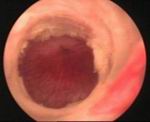

• A look into the urethra by a special thin telescope will be needed to assess the stricture.

In this procedure, a thin telescope is passed into the urethra to see exactly where the stricture is. This is done during a general anaesthetic. A tiny knife is then passed down the telescope to cut along the stricture. This widens the narrowed stricture. You will get some relief of symptoms from this procedure. About one case in three is cured for good. However, like dilation, the stricture may re-form and the procedure may have to be repeated from time to time in some cases.